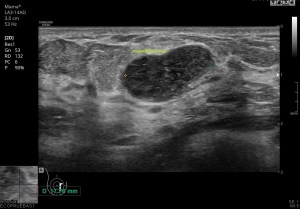

248. Clasificación Bi-Rads.

Hace mucho tiempo que quería dedicar un Post a explicar  la clasificación Bi-Rads, pero en imágenes. Como es de todo el mundo sabido la clasificación Bi-Rads es la clasificación que usan las radiólogas para establecer una sospecha radiológica con respecto a la exploración que se realiza, habitualmente, mamografía, ecografía de mama o resonancia magnética de mama.

Aunque es habitual que una paciente sea explorada con mamo y eco, este post voy a dedicarlo a la parte ecográfica, por motivos obvios.

Voy a ir desgranando los diferentes grados de clasificación de esta escala, desde el 0 al 6 y en aquellos determinantes, voy a colocar una imagen explicativa, que obviamente y menos en un estudio como la mama, no es el hallazgo típico, es decir, que la cantidad de patología y semiología de ésta, en la mama es muy variada y varias lesiones, completamente distintas en su aspecto ecográfico pueden compartir misma clasificación.

Clasificación por porcentajes de sospecha que te empiezo a desgranar en imágenes.

Birads 2: Existen hallazgos patológicos que la radióloga encuentra como hallazgos benignos, con confundir con normalidad, la exploración ha arrojado hallazgos patológicos, pero son benignos.

Quistes simples, fibroadenomas, lipomas mamarios o ganglios intramamarios son alguno de estos hallazgos.

Bi-RADS 2. Quiste simple.

Semiología habitual de los hallazgos benignos:

-Forma elíptica o ligeramente lobulada

-Más grande en eje transverso, es decir, que de derecha a izquierda son mayores que desde anterior a posterior.

Isoecoica o ligeramente hipoecogénica

-Buena transmisión de sonido

-Cápsula ecogénica delgada

-Sombras laterales finas

Birads 3: Benignidad en torno al 98% de posibilidades. Son hallazgos patológicos, que normalmente requieren revisión para confirmar estabilidad, dos años, periodo en el cual si la lesión no ha cambiado de aspecto, se rebajará el estadiaje a Birads 2.

Bi-RADS 3. Fibroadenoma.

Birads 5: Los hallazgos sugieren malignidad en porcentajes muy altos.

Bi-RADS 5. Heterogenicidad y bordes irregulares en el nódulo.

Birads 6: Malignidad confirmada. Cuando todas las pruebas realizadas, desembocan en un diagnóstico de malignidad apoyadas en pruebas de imagen, Mamo, Eco y RM y los resultados de anatomía patológica que habrá certificado dicha sospecha, confirmándola.

Bi-RADS 6. Altísima sospecha por irregularidad de bordes, defecto de transmisión, calcios internos…